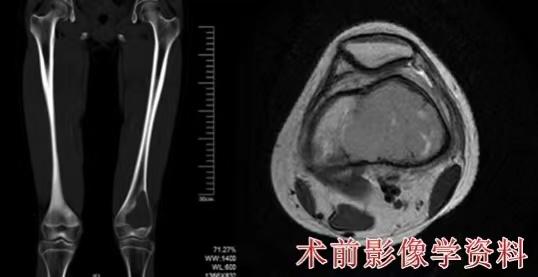

52143672_e59e9978-db8c-47ed-b2eb-9bd60f6c2f6d.jpg

小刘(化名)术前影像资料 受访者供图

患者小刘(化名)同样因右小腿酸痛伴跛行前往当地医院就诊发现右胫骨肿物,随后转至 ,检查确诊为右胫骨干中段骨肉瘤。

医院骨肉瘤MDT团队讨论,认为患者存在保肢治疗指征,在前期新辅助化疗顺利开展下,决定采用右胫骨干中段骨肉瘤根治性切除+同侧带血管蒂腓骨移植、异体骨重建+钢板螺钉内固定的方式进行重建。

通过移植带血管蒂的腓骨,重新构建了血液循环,促进了骨断端的愈合,减少了骨不连的发生概率,同时,考虑到青年男性体格较大,纤细的腓骨不能满足早期负重和功能锻炼的需求,因此术中加用了异体骨植骨+长锁定钢板的方案,增强了重建节段的局部稳定性。